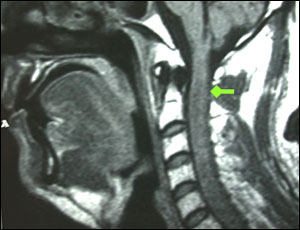

女性,65岁,左上肢麻木半年,呼吸乏力1周。查体:左侧颈2-3分布区针刺痛觉减退,左侧咽反射迟钝,悬雍垂右偏。

术前图片